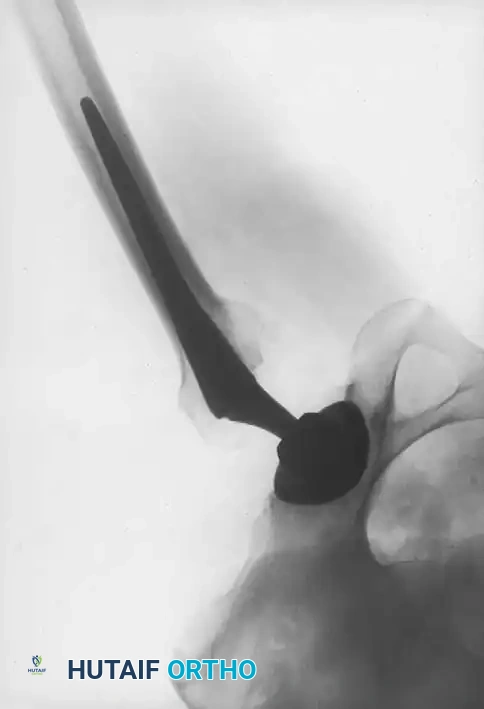

Standard preoperative radiographs must include an anteroposterior (AP) view of the pelvis centered over the pubic symphysis (with the hips internally rotated 15 degrees to profile the femoral neck) and a lateral view of the affected hip.

1. Determine Leg Length Discrepancy: A horizontal reference line is drawn across the bottom of the radiographic teardrops or the ischial tuberosities. The difference in the perpendicular distance from this line to a reproducible landmark on the proximal femur (usually the lesser trochanter) approximates the amount of limb shortening.

2. Acetabular Templating: The acetabular template is positioned at a 40- to 45-degree angle of inclination. It should correspond closely to the subchondral bone plate, ensuring adequate lateral coverage and medialization to the true floor (ilioischial line). The new center of rotation is marked.

3. Femoral Templating: The femoral template that most closely matches the proximal and distal size and contour of the femoral metaphysis and diaphysis is selected.

4. Neck Length and Offset: The neck length and offset are estimated to restore the abductor moment arm. The anticipated level of the femoral neck resection is marked relative to the lesser trochanter.

Fig. 7-40 Templating of radiographs for preoperative planning. A, Line drawn across the bottom of the pelvis to assess limb shortening. B, Acetabular template placed to mark the new center of rotation. C, Femoral template matching the metaphysis. D, Neck length and offset estimation.